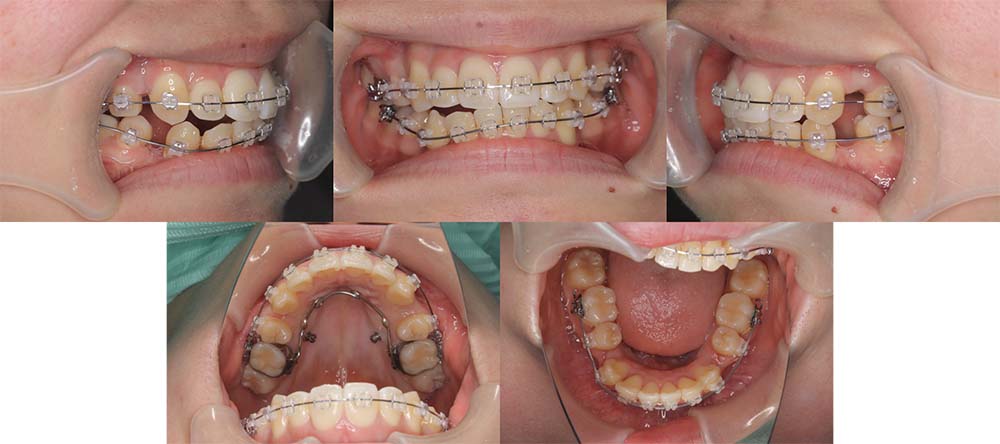

| 症例分類 | 下顎前突、開咬 |

| 診断名 | 上下叢生を伴う開咬 |

| 主訴 | 歯がガタガタ、前歯に隙間があってうまく噛めない |

| 年齢 | 18歳4ヶ月 |

| 性別 | 女性 |

| 抜歯部位 | 右上・左下の第一小臼歯と左上・右下の第二小臼歯 |

| 使用装置 | 表側のワイヤー装置 |

| 治療期間 | 2年9ヶ月 |

| 保定装置 | 固定式保定装置、取り外し式保定装置(8時間) |

| 費用 |

[検査・診断料] ¥49,500 [基本施術料] ¥792,000 [調整料] ¥4,400/回 [抜歯] ¥5,500/本 [保定装置] ¥55,000(税込) 抜歯や虫歯治療は他院にて費用が別途かかります。(抜歯¥4,000〜10,000/本)

他院にて「顎変形症のため手術併用での矯正治療が必要である」との説明を受け、当院を紹介されてご来院されました。骨格的にやや受け口傾向ではありましたが、手術を併用せず改善できる旨をご説明し、矯正単独で治療することにしました

上顎右側第一小臼歯、上顎左側第二小臼歯、下顎右側第二小臼歯、下顎左側第一小臼歯を抜去して治療を行いました。

左下は奥歯を前方に移動させる必要があったため、矯正用アンカースクリューと顎間ゴムを使用して噛み合わせを改善しました。左下の前方移動に時間がかかってしまい、治療期間が予定より伸びてしまいましたが、問題なく咬合させることができました。

下顎の親知らずは将来的に抜去した方が良いことを説明しております。